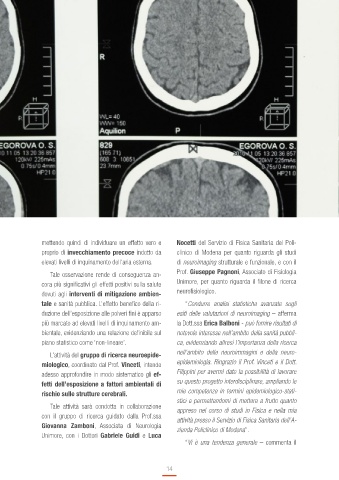

L’attività del gruppo di ricerca neuroepide- nell’ambito delle neuroimmagini e della neuro-

miologico, coordinato dal Prof. Vinceti, intende epidemiologia. Ringrazio il Prof. Vinceti e il Dott.

adesso approfondire in modo sistematico gli ef- Filippini per avermi dato la possibilità di lavorare

fetti dell’esposizione a fattori ambientali di su questo progetto interdisciplinare, ampliando le

rischio sulle strutture cerebrali. mie competenze in termini epidemiologico-stati-